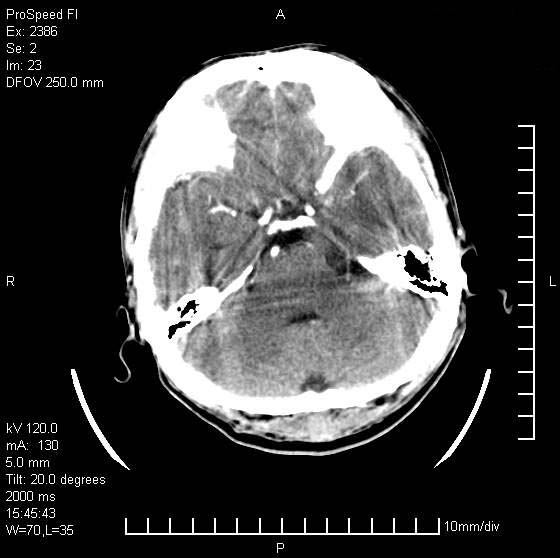

以下是引用天南地北在2007-9-19 18:43:00的发言:[br]典型慢性硬膜外血肿[br][br][本贴已被 天南地北 于 2007-9-19 18:44:11 修改过]

以下是引用曼一拍在2007-9-20 11:06:00的发言:[br]支持慢性硬膜下血肿.[br]慢性硬膜下积液:血肿有包膜,ct值稍高于脑脊液,增强可有染色。不典型者血肿可多呈梭形.是硬脑膜与蛛网膜之间的潜在腔隙内的血肿。[br]鉴别:[br]1\\硬膜外血肿:是颅脑外伤后脑膜或板障内血管破裂,血液在颅骨与硬膜之间积聚所致.通常是脑膜动脉破裂,也可因静脉窦破裂或颅骨的板障静脉出血,发生于外伤的着力部,常与颅骨骨折并存。脑膜动脉出血则急,若是板障静脉出血在则可有慢性。[br]2\\硬膜下积液:(硬膜下水瘤)[br]是由于蛛网膜破裂,脑脊液经蛛网膜破口进入硬膜下腔不能回流。或水肿阻塞而形成。[br]ct表现:颅骨内板下方新月形低密度区近似脑脊液密度;占位效应清,周围无脑水肿。[br]